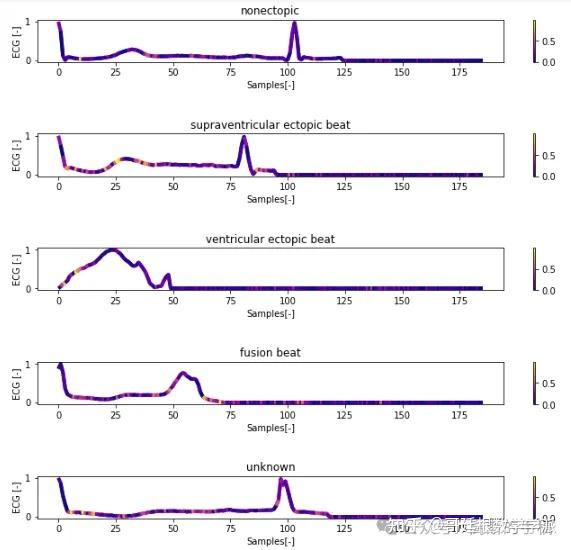

一维神经网络的特征可视化分析-以心电信号为例(Python,Jupyter Notebook)

包括Occlusion sensitivity方法,Saliency map方法,Grad-CAM方法